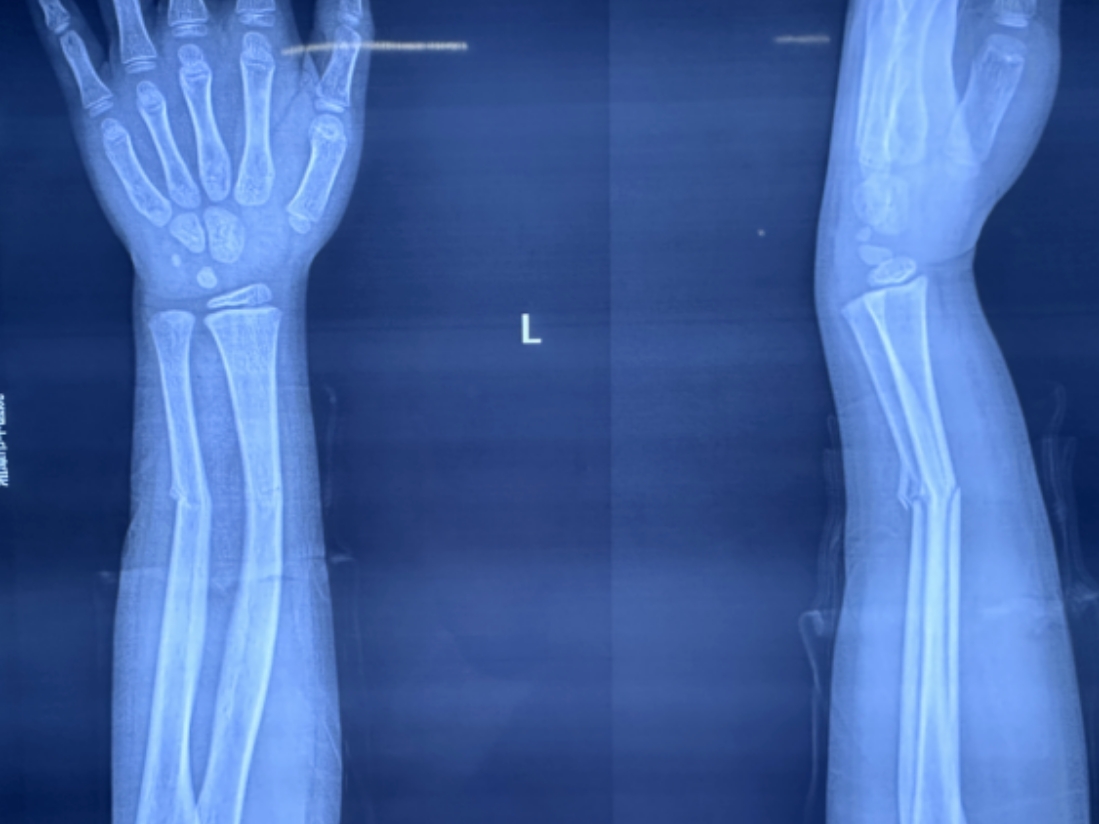

尺橈骨雙骨折復(fù)位前 尺橈骨雙骨折復(fù)位后